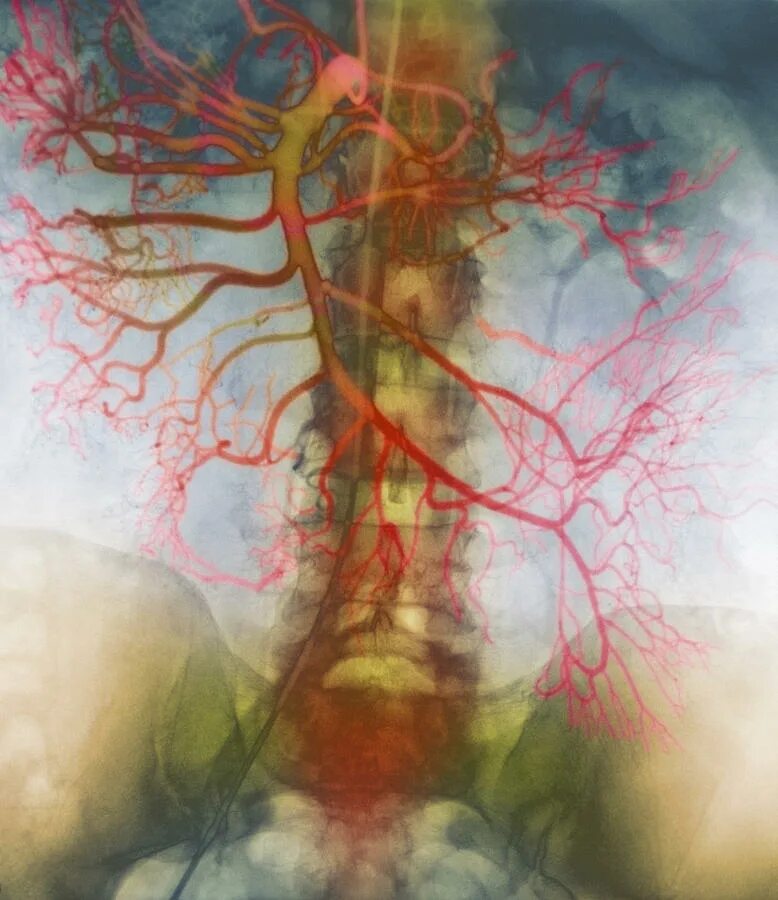

Тромбоз брыжеечной артерии